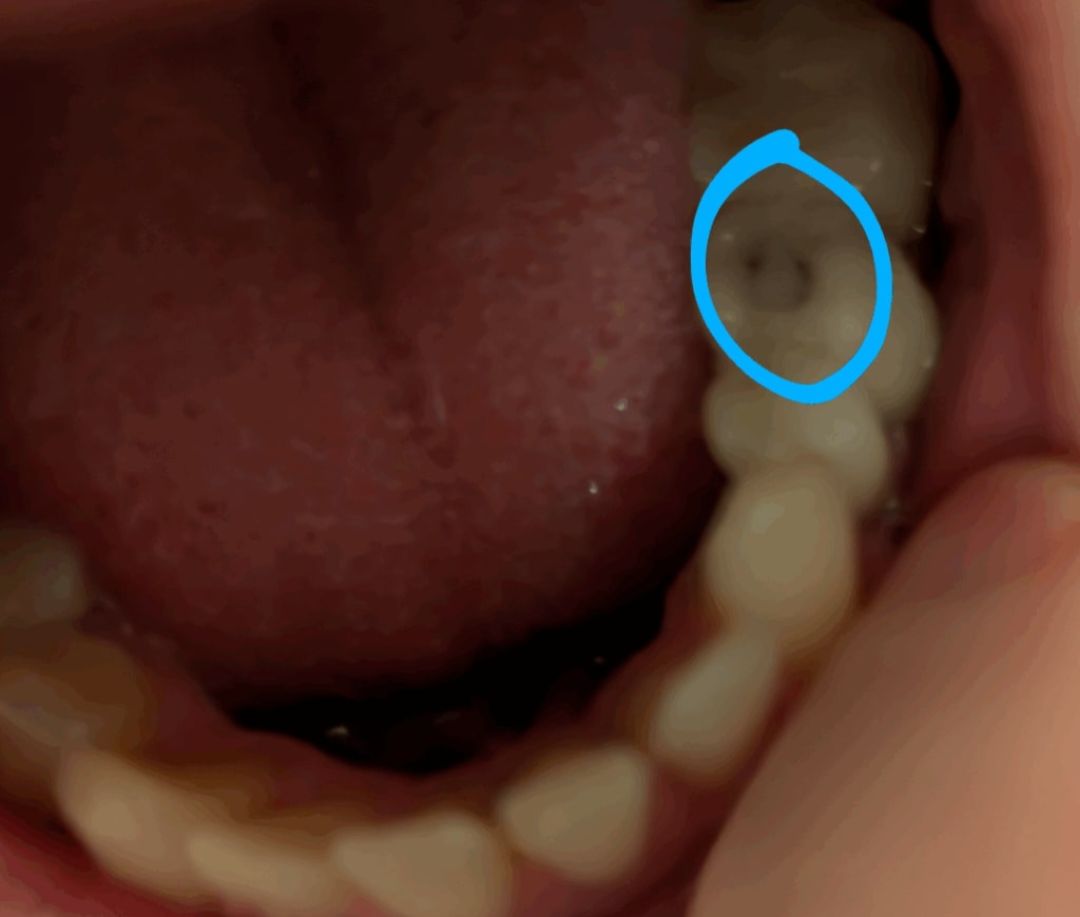

Debido a las inflamaciones resultantes, los tres dientes afectados (26, 35 y 36) requirieron un tratamiento de conducto radicular. Esperaba que la pesadilla hubiera terminado, pero poco después, el sello del diente 35 se rompió a los pocos días de haberlo hecho. Se lo mostré, pero me dijo que no era ningún problema y me mandó a casa. Días más tarde, el diente empezó a dolerme mucho cada vez que algún líquido tocaba la grieta: